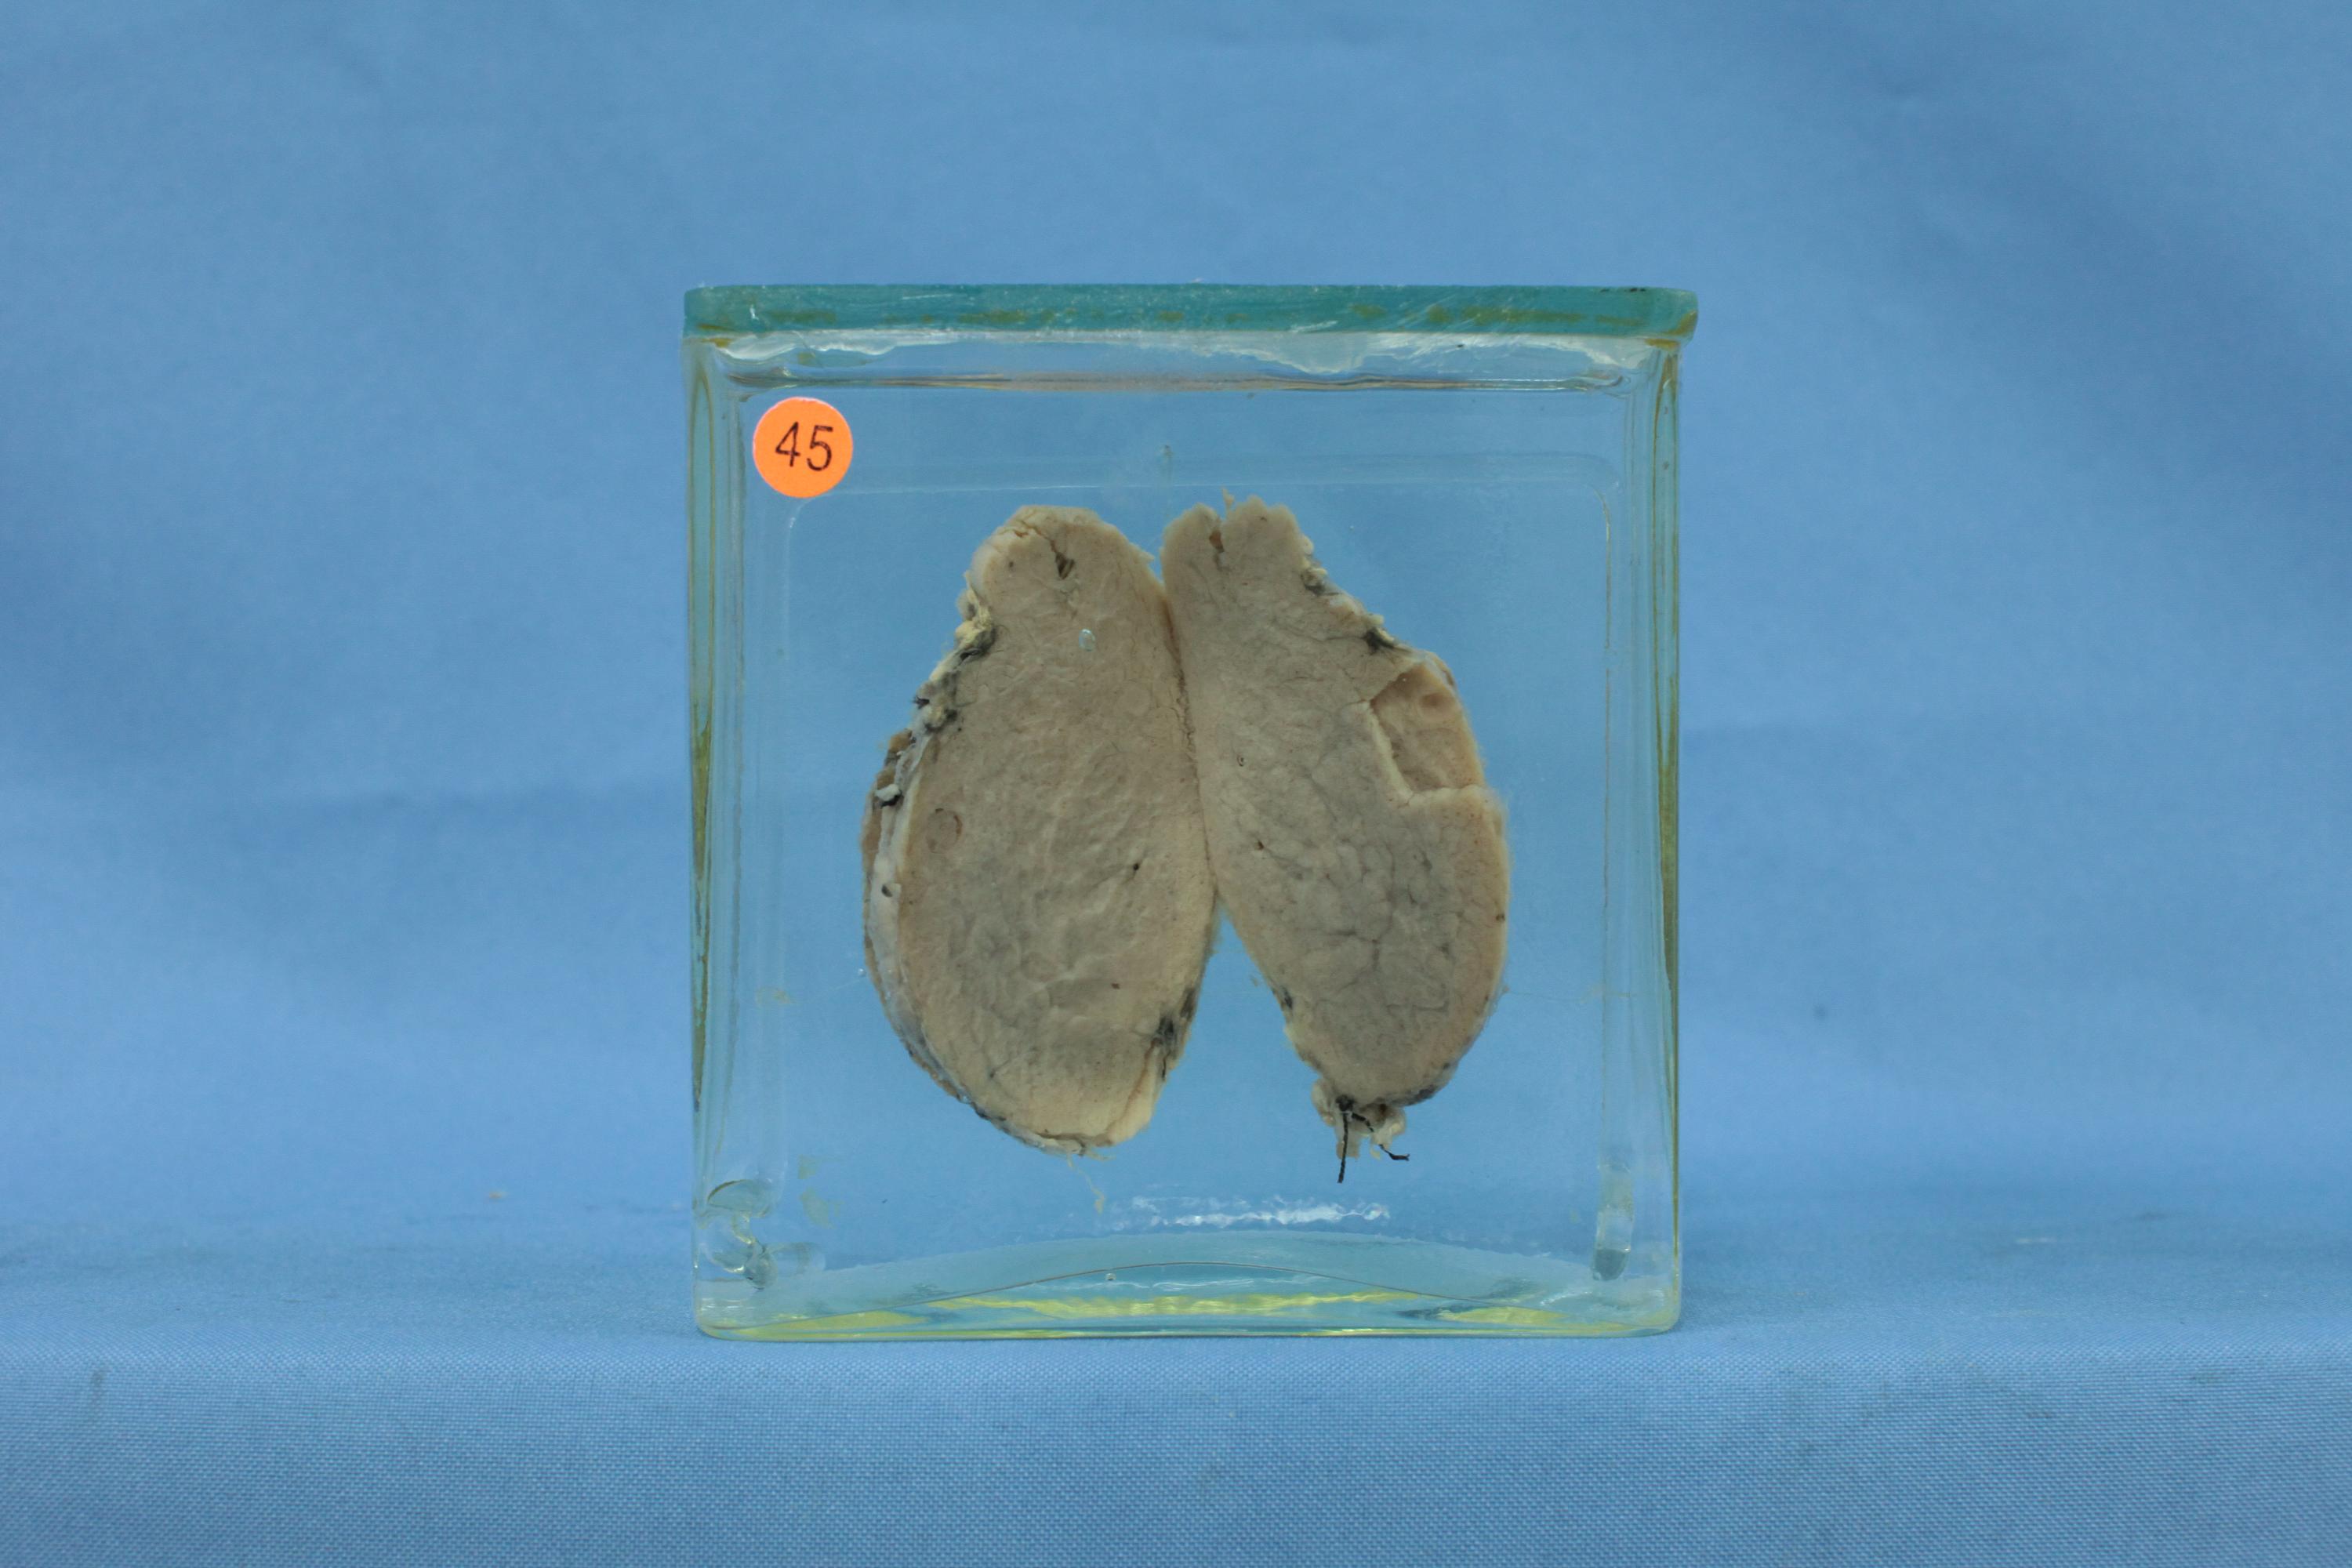

内分泌-71-45. 甲状腺功能亢进(Graves病)

甲状腺体积较大,切面呈灰黄色,结构致密似肌肉状。